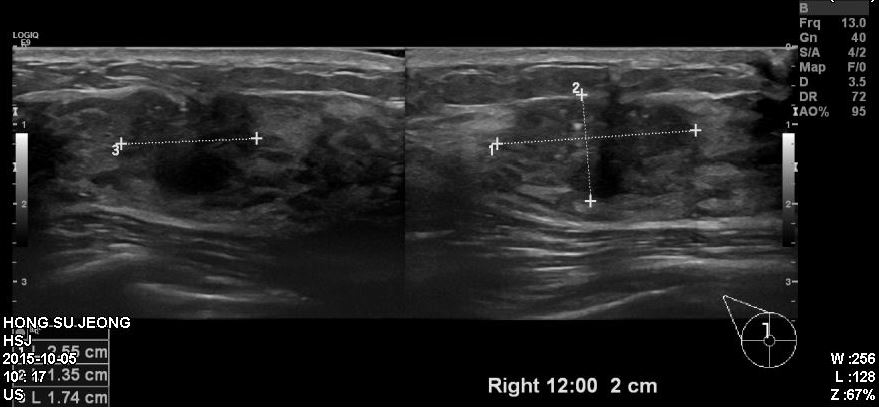

건진상 이상소견으로 내원하신 30대 환자분이십니다.

타원에서 시행한 유방초음파상 우측 12시방향에 의심되는혹 확인되어

본원에서 조직검사 시행하였고

결과상 침윤성유관암 진단되었습니다.